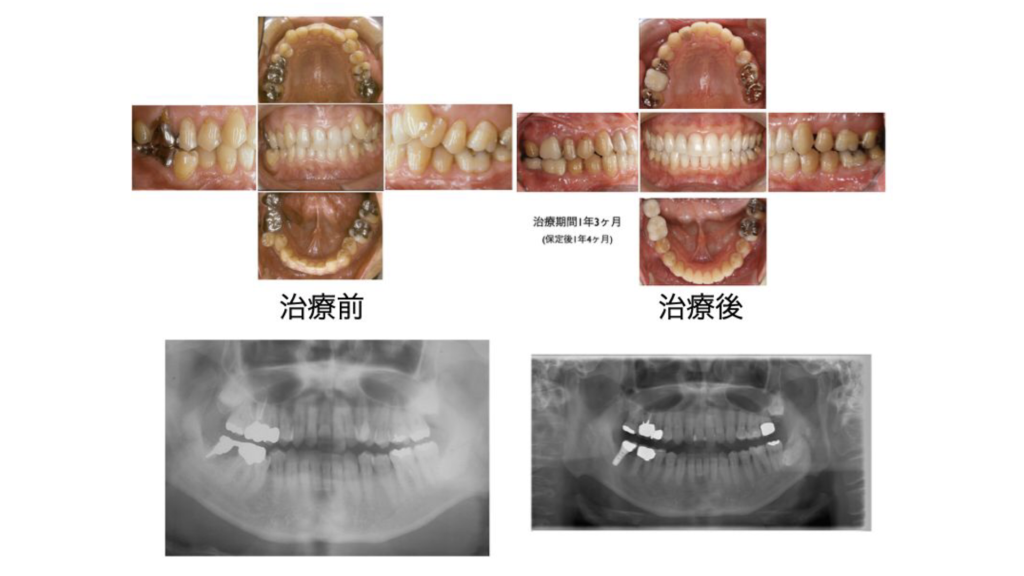

コルチコトミー併用矯正+インプラントの13年経過症例~40代男性~

治療当時40代男性の症例です。

噛み合わせの改善を主訴に来院されました。

全顎的にはコルチコトミー(皮質骨への画家的な切開)併用のスピード矯正右下奥歯には、インプラント治療を行なっています。

現在治療後13年経過して定期的なメンテナンスを行っています。